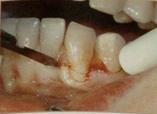

4.Bruno (1994) – модификация метода Langer и Langer без вертикальных разрезов, что улучшило эстетический результат и увеличило площадь кровоснабжения трансплантата. Разрез у сосочков проводится под прямым углом для плотного сопоставления и ушивания краев трансплантата и донорской раны «стык в стык». Трансплантат всегда помещается на надкостницу, поэтому ткани расщепляются на первичный лоскут и принимающее ложе. Для ушивания без натяжения проводится широкая препаровка в основании и по боковым краям первичного лоскута. Для надежной фиксации трансплантата используются позиционирующие (фиксация в нужном положении) и фиксирующие швы (удержание на принимающем ложе).